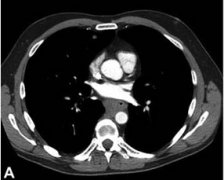

• Barrett食管綜述-巴雷特氏食管

食管下段的鱗狀上皮被柱狀上皮覆蓋,因為英國人Barrett首先報道,因此稱 Barrett食管 ,中文翻...

• Barrett食管癥狀及檢查

常見癥狀 便血 惡心與嘔吐 燒心 吞咽困難 胸骨后疼痛 BE本身并無癥狀,其癥狀主要是由于胃食...